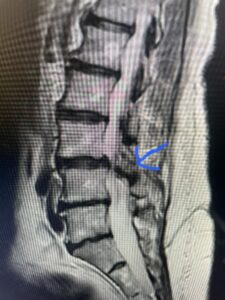

Another patient is a 62 year-old female with progressive low back pain and right leg pain and numbness that radiates to the top of her foot. She tried physical therapy and epidural injections. MRI demonstrated severe L3-4 stenosis and a grade 1 spondylolisthesis (Fig 4). There was L5-S1 and L4-5 disc collapse with modic end-plate changes. Biomechanically because of the significant degeneration of these disc spaces which stiffened the L4-S1 segment more stress was placed on the L3-4 segment, resulting in significant premature degeneration and compensatory stenosis and segmental instability. The MRI also showed pathologically, because of the slip, the L3 inferior processes were more anteriorly oriented and hence contributing to the majority of the lumbar canal compromise. Note the more sagittally-oriented facets in this case compared to the prior case (Fig 5). The patient underwent a decompressive laminectomy with attention of removing the inferior processes of L3 to fully decompress the canal. We also performed an L3-4 fusion with instrumentation (Fig 6). The patient had an uneventful postoperative course with improvement of leg pain. Of note with relief of the disabling leg pain patients are generally very happy. Patients can often manage their low back pain; it is the leg pain that they just can’t tolerate.

Fig 4: Sagittal T2-weighted lumbar MRI demonstrating L3-4 grade 1 spondylolisthesis with severe stenosis (blue arrow)